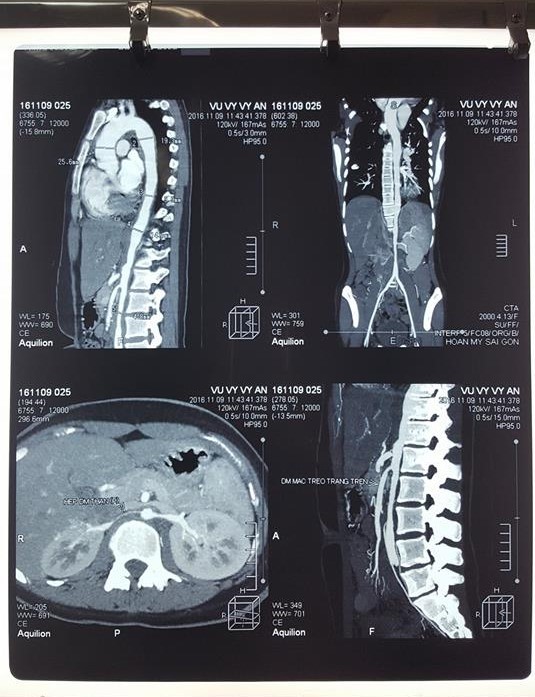

Kết quả chụp CT động mạch có cản quang sau đó đã xác định chẩn đoán ban đầu này. |

Trong trường hợp bệnh nhân V.V.A, do đặc điểm cao huyết áp người trẻ, đau 2 chân khi hay gắng sức, kèm theo âm thổi động mạch thận 2 bên, kết hợp nhiều triệu chứng gợi ý khác nên các bác sĩ đã chủ động chẩn đoán chứng bệnh Takayasu và kết quả là chính xác với hình ảnh tổn thương lan tỏa động mạch chủ và động mạch thận 2 bên trên CTscan mạch máu có thuốc cản quang.

Hình ảnh tổn thương lan tỏa động mạch chủ với rất nhiều chỗ phình và hẹp được ghi nhận. |